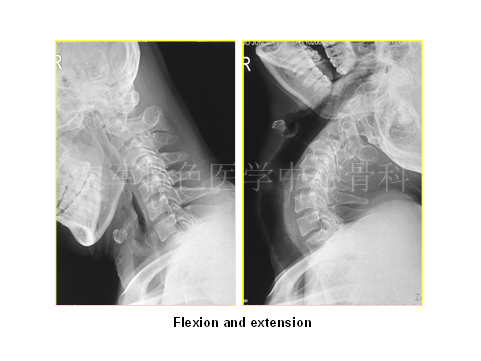

最终陈医生采取的治疗方案与各位专家不谋而合,患者最终行颈后路C3-6椎管扩大成型术,术后患者自觉症状明显减轻,JOA评分:12分。术后3年随访,患者步态稳健,无明显不适。

随访影像学如下:

专家点评:对于影像学可以解释的神经压迫症状,临床还是建议积极手术治疗。该患者脑瘫诊断不明确。帕金森患者由于长期头部晃动,可能会产生脊髓刺激,临床应认真查体,仔细核对影像学,尤其应与脊髓硬化症相鉴别。脊髓硬化症手术会加重患者临床症状。同时,应积极请神经内科会诊,协助鉴别。